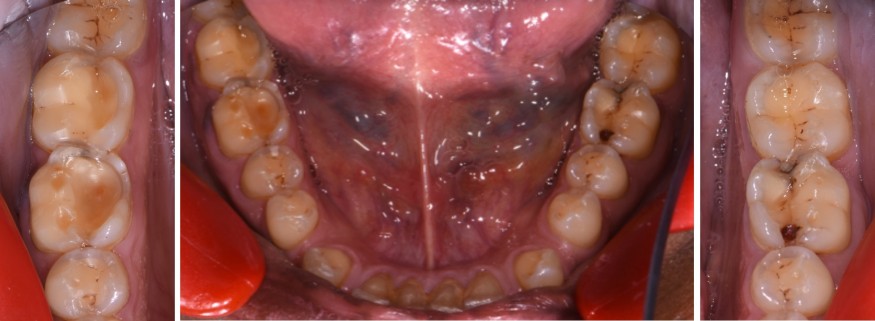

- Exposition dentinaire, due à la perte d’émail ou de cément, par abrasion (brossage traumatique), érosion (acides), attrition (bruxisme) (fig. 3-7), ou anomalies de structure (MIH**, amélogenèse imparfaite) [5].

(Crédit photo : Olivia Kérourédan) - Figure 4. Lésions érosives palatines au niveau du secteur incisivo-canin maxillaire, suggérant une acidité d’origine endogène.

(Crédit photo : Olivia Kérourédan) - Figure 5. Association de lésions d’usure d’origine érosive, abrasive et attritionnelle.